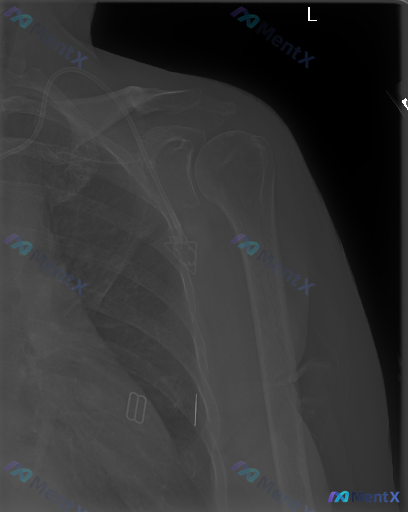

整理到一张左侧肩部正位X线平片的分析资料,图像里能看到锁骨下、腋下及胸廓侧壁有几处高密度金属影。